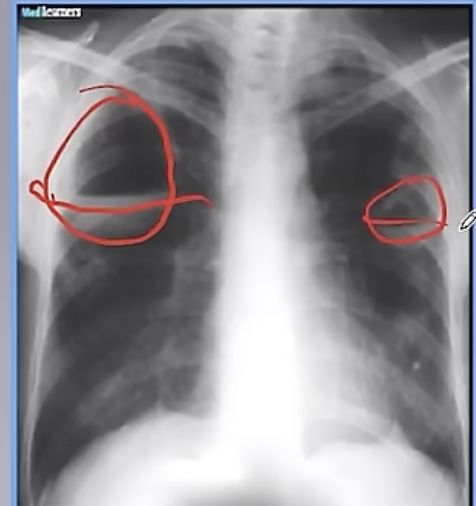

Q

Imagen de neumonia multilobar

A

son atipicas y se dan en inmunocomrpometidos